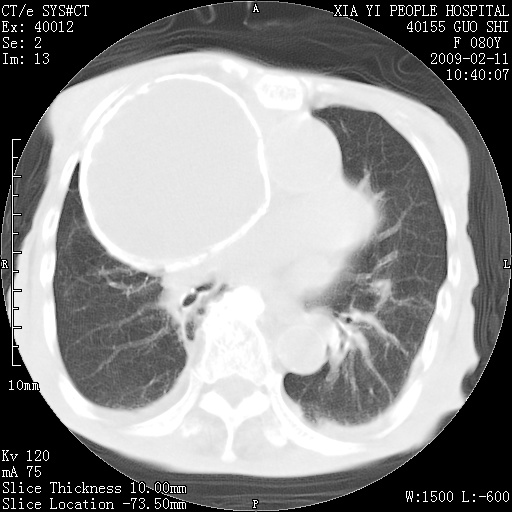

以下是引用随光逐影在2009-2-16 16:34:00的发言:[br]1)考虑右前纵隔皮样囊肿。2)双侧少量胸腔积液。

以下是引用zjzjr在2009-2-16 17:30:00的发言:[br]支持囊性畸胎瘤 双侧少量胸腔积液。